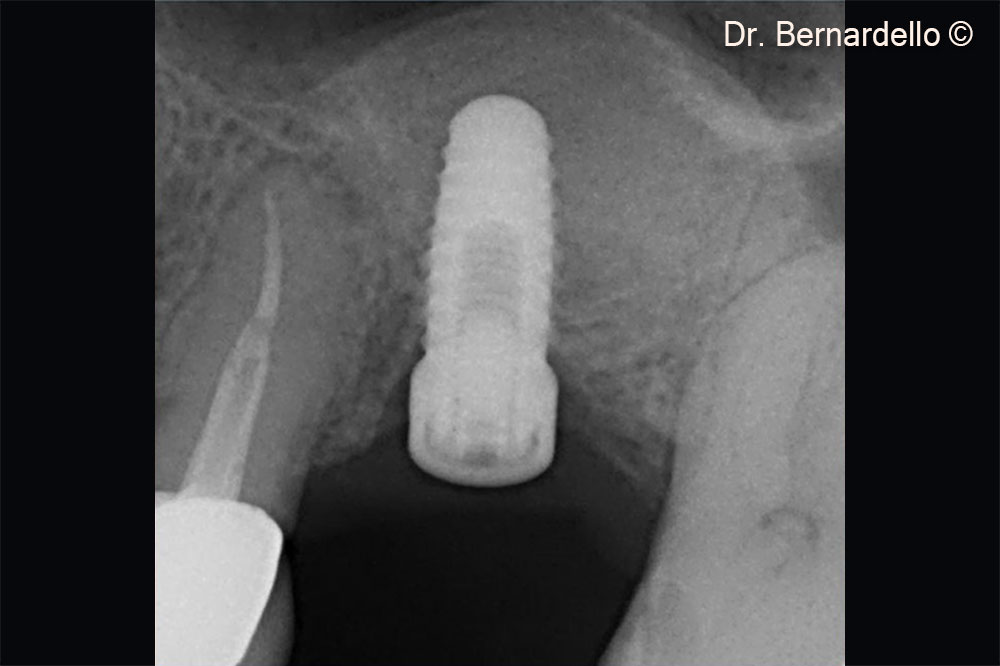

Gel 40 is used to detach the Scheiderian membrane

Immediate implant insertion